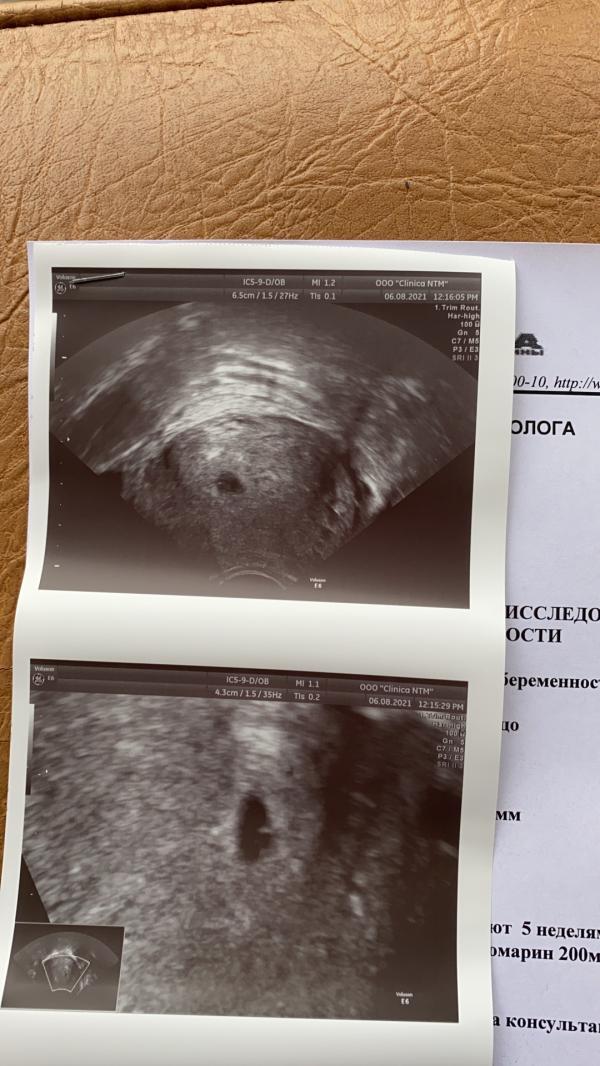

❤️Наше первое УЗИ 😍